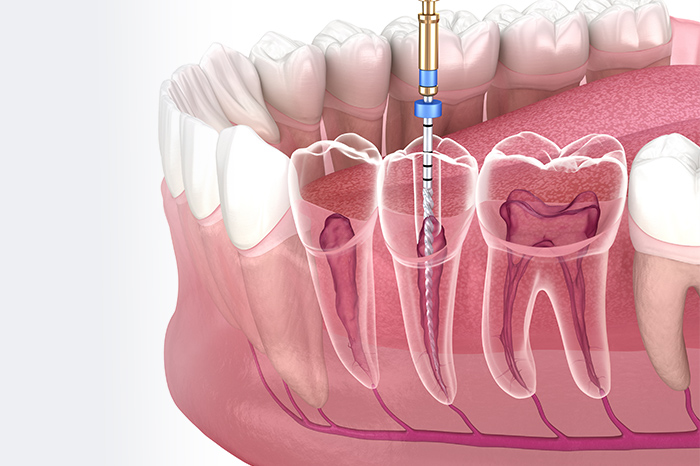

「根管」とは、歯の根の内部にある細い管で、神経や血管が通っています。むし歯が根管まで達すると、ズキズキとした痛みを伴うようになり、歯の根がダメージを受けて抜歯を余儀なくされる場合もあります。根管内のむし歯に侵された部分を取り除き、洗浄・消毒、密閉するのが根管治療です。歯の根を守ることができれば、抜歯を避けられる可能性があります。

マイクロスコープを

活用した精密な治療

根管の内部は細く、暗く、複雑な構造をしているにも関わらず、以前は歯科医師の経験と勘を頼りに処置を行わなければなりませんでした。当院ではマイクロスコープ(歯科用顕微鏡)を導入しており、最大20倍程度にまで患部を拡大して治療を行います。さらに明るいライトで照らすことで、より精密な処置を行えるのが特徴です。